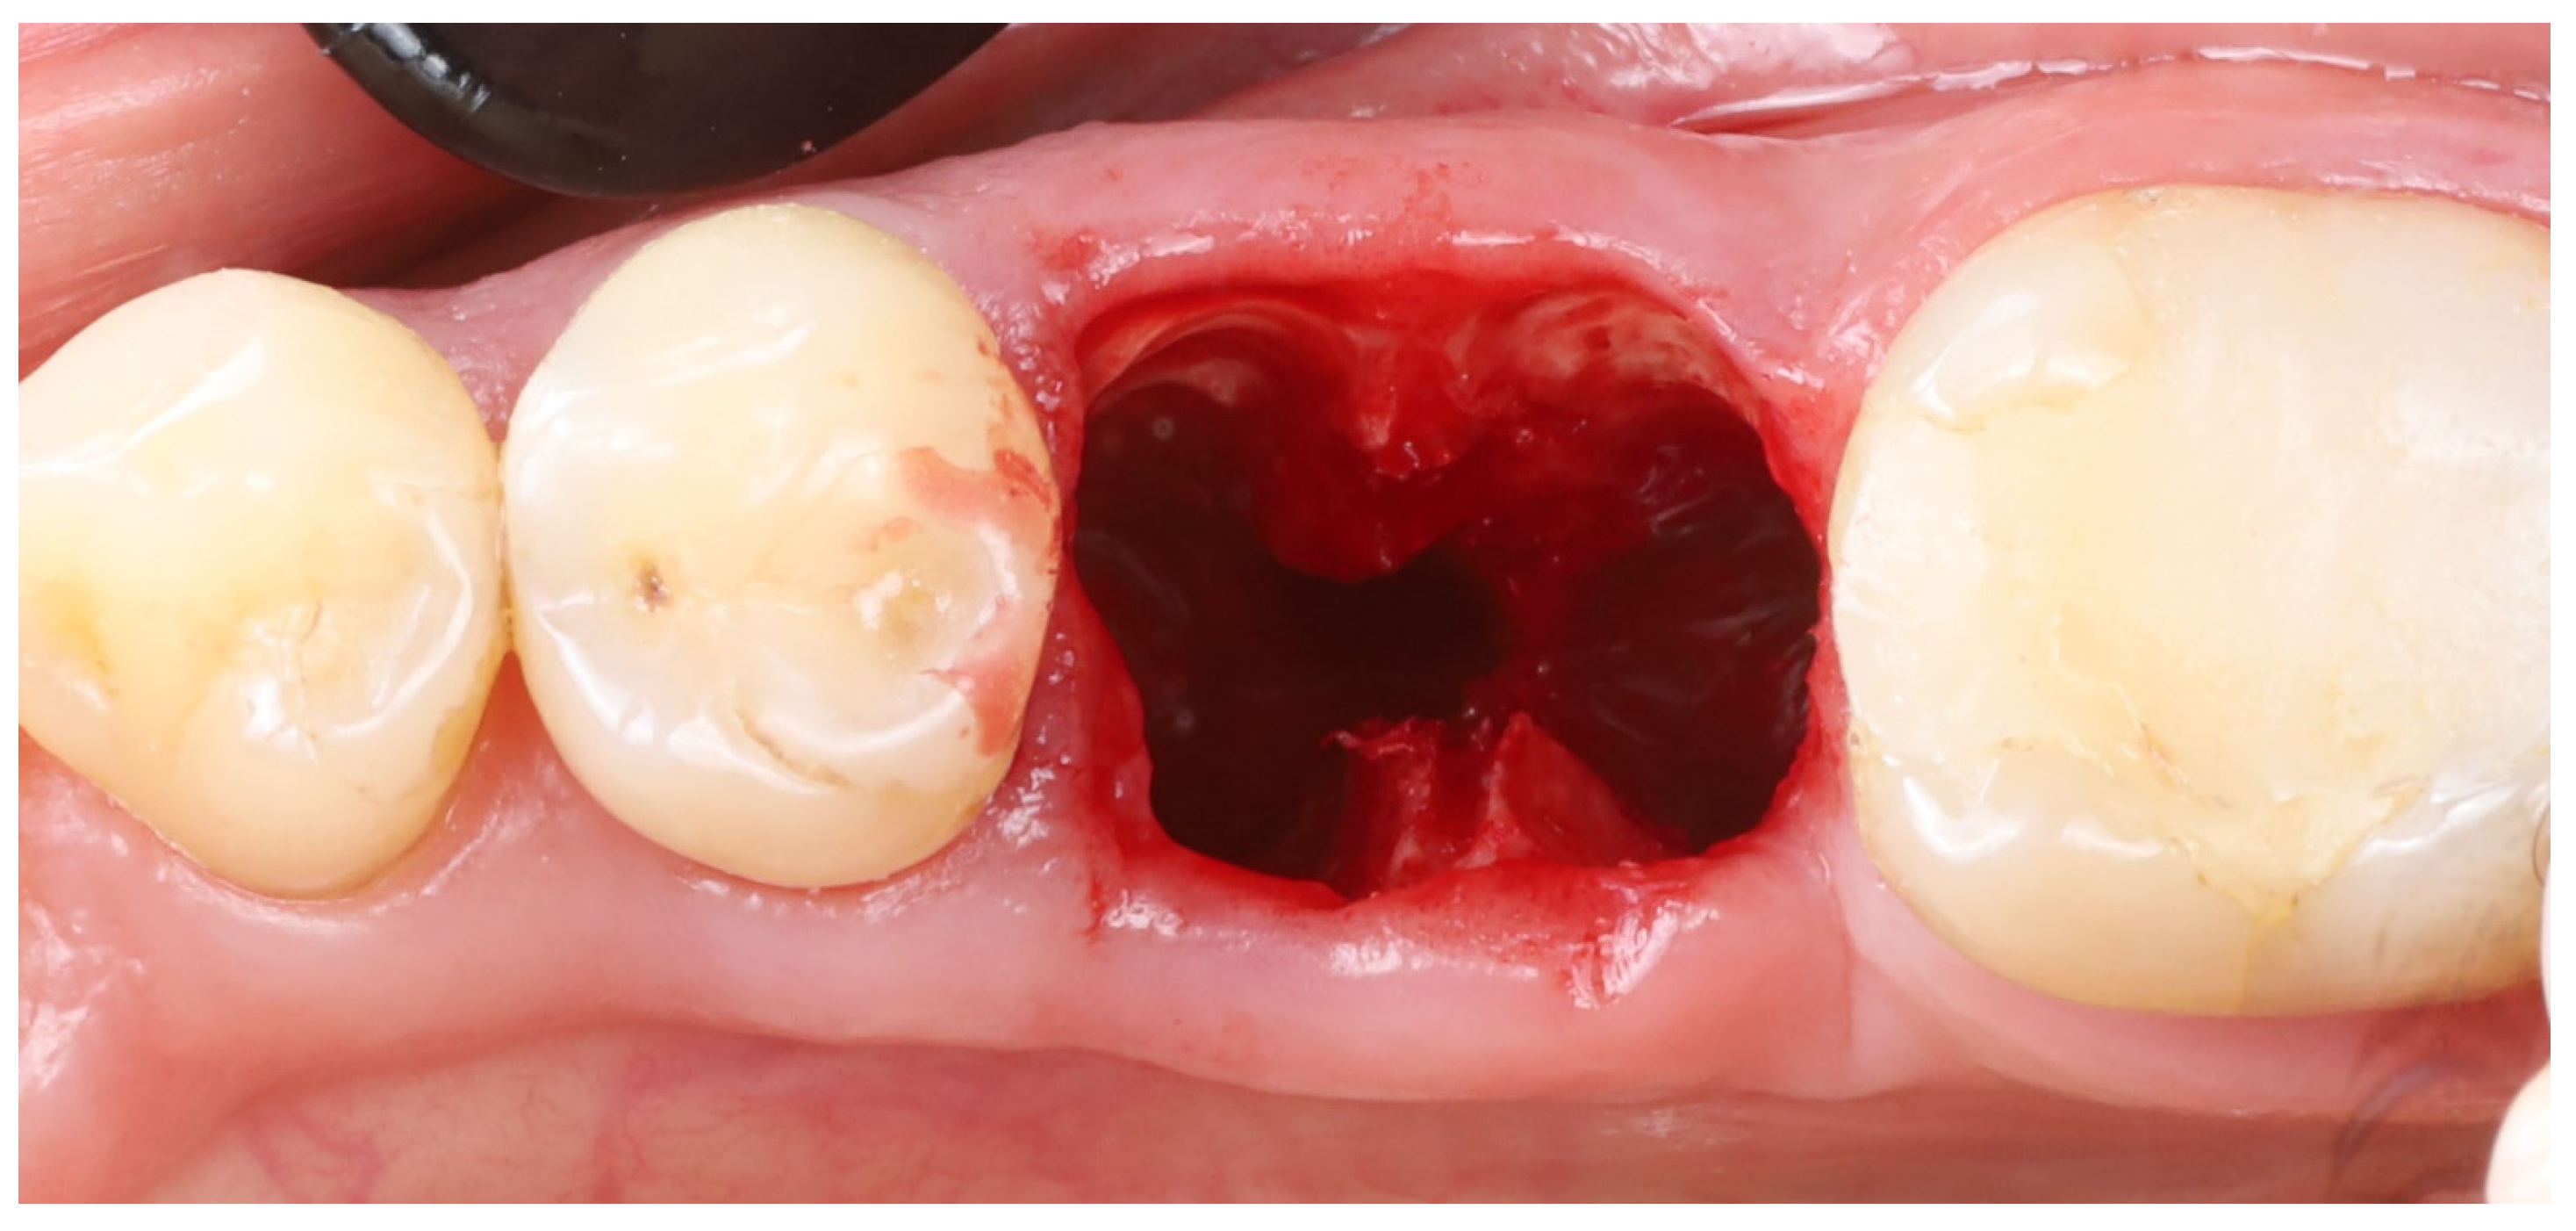

- Root sectioning: After performing mandibular nerve block anesthesia, the crown of tooth #36 (Figure 2A) was removed (decoronation was performed) (Figure 2B). The mesial and distal roots were then separated buccolingually using a long-shanked, straight diamond bur in a high-speed handpiece with copious irrigation (Figure 2C). The preoperative CBCT was consulted to guide the depth and orientation of the cuts, accounting for the roots’ length, curvature, and angulation.

- Partial root extraction: Each root was sectioned in a mesiodistal direction approximately 1–1.5 mm buccally from the center of each root surface to a depth of about two-thirds of the root length, using a #2 long cylinder bur from Gluckman’s partial extraction therapy (PET) surgical kit (Megagen, Seoul, South Korea). This created buccal and lingual segments for each root. The lingual root segments (along with their apices) were carefully extracted, leaving only the buccal portions of the roots in place as the “socket shields” (Figure 2D). If the lingual part fails to extract and remains in the socket still attached to the shield, it should be detached from the shield with bur #3 and extracted in the conventional way. In such cases, the bony septum can be drilled in the center to facilitate extraction.